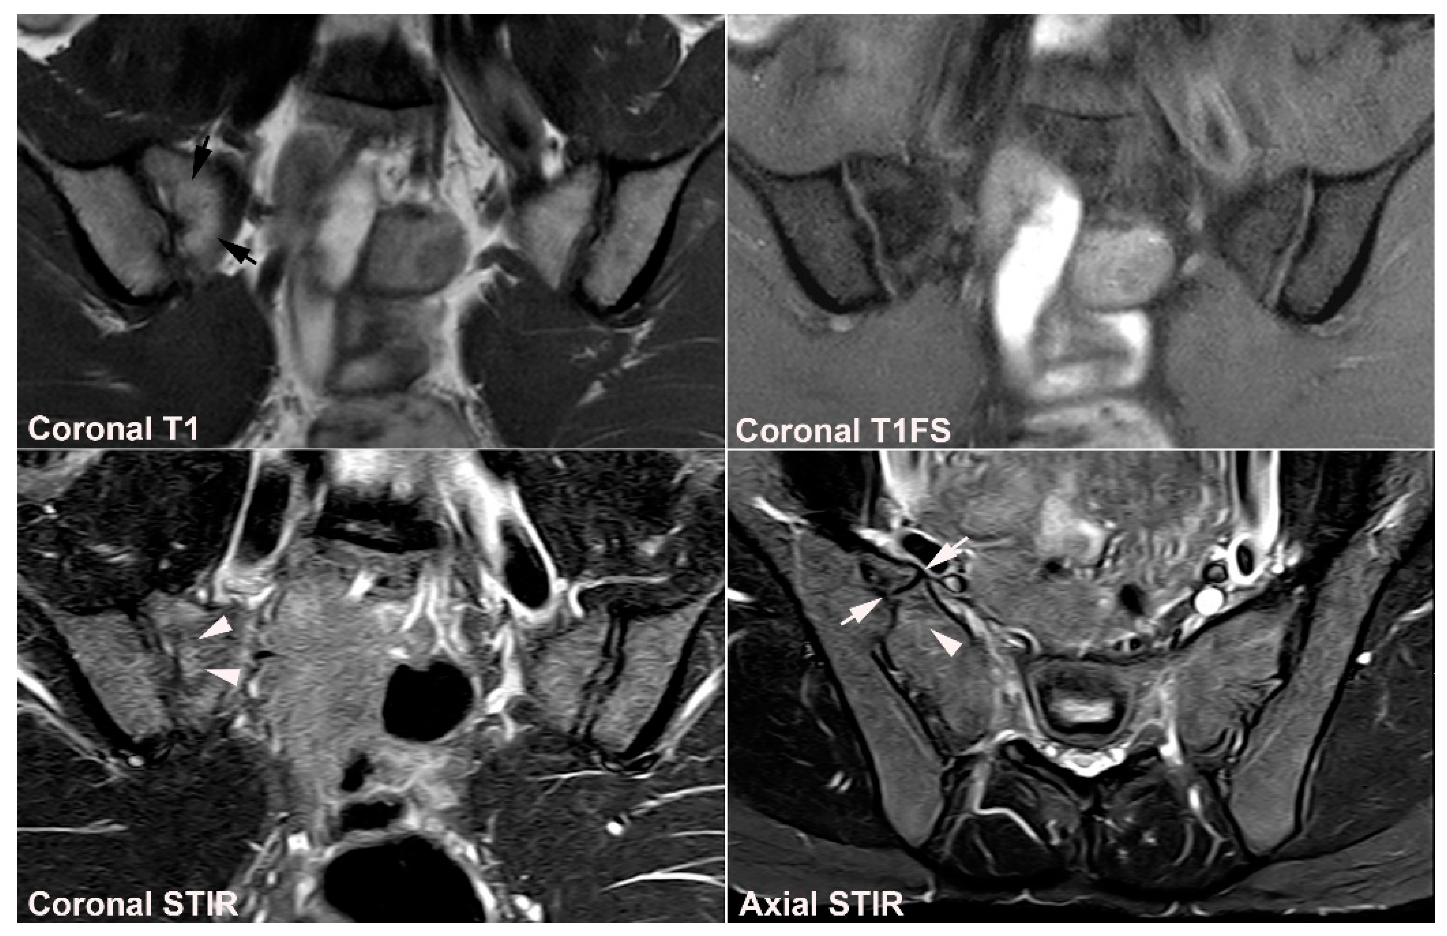

11.2. Chronic Non-Bacterial Osteitis (CNO)

12. Hyperparathyroidism and Other Disorders of Mineral Metabolism

13. Tumors